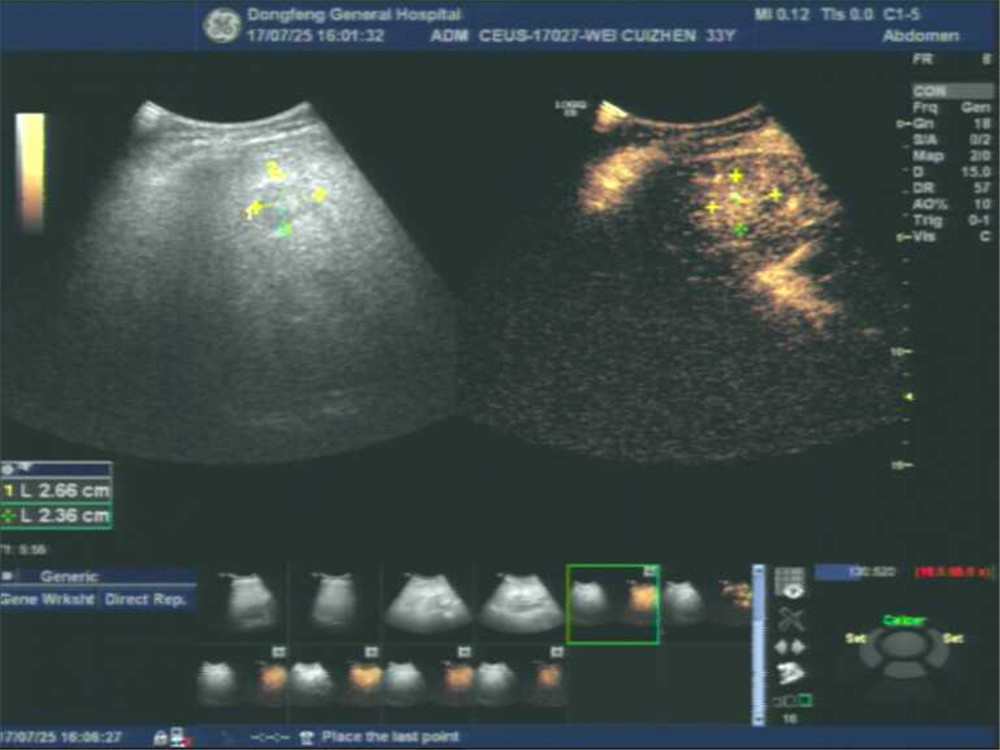

下图为肝脏局灶性结节超声造影及二维超声对比图。

IMG_256